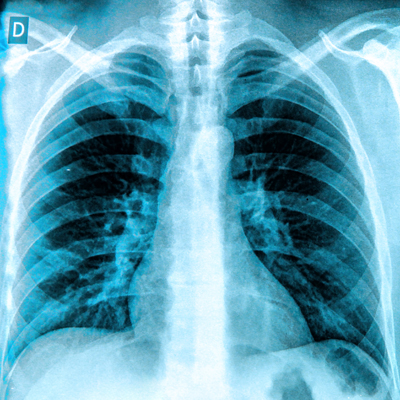

AI-assisted triage of lung x-rays using commercially available software can help reduce turnaround times in real-world settings by 77%, according to an article published on 10 October in the European Journal of Radiology.

A group led by Srinath Sridharan, PhD, of Changi General Hospital in Singapore, also found that the software (CXR Triage, Lunit) achieved a specificity of 99% in urgent cases and thus could aid in critical decisions.

CXR Triage received clearance from the U.S. Food and Drug Administration (FDA) in 2021, yet evidence is lacking on its usefulness in mainstream clinical settings, the authors explained. The software is designed to triage chest x-rays as normal, nonurgent, or urgent, and has previously demonstrated high accuracy in detecting pneumothorax and pleural effusion, for instance.

In this study, the researchers integrated the software into their hospital’s PACS. Between August 2023 and December 2023, 43 radiologists approved 20,944 chest x-ray reports that the AI had triaged into normal, non-urgent, and urgent. The images were acquired in the hospital’s emergency department.

Out of the 20,944 chest x-rays, 28.6% were normal, 61.2% were nonurgent, and 10.2% were urgent. According to the analysis, the AI system demonstrated a sensitivity of 89% in correctly identifying normal CXRs, with a specificity of 93%.

“This suggests that the software is highly reliable in detecting cases without abnormalities, indicating a reduced likelihood of false positives in normal [chest x-ray] classifications,” the authors wrote.

For nonurgent chest x-rays, the software exhibited a sensitivity of 93% and a specificity of 91%, indicating robust performance in identifying chest x-rays that do not require immediate attention, they suggested.

In the urgent category, the software achieved a sensitivity of 82% and a specificity of 99%, demonstrating its potential utility in clinical settings for flagging conditions that need immediate intervention.

In addition, in an analysis of turnaround times, AI outperformed radiologists in minimum turnaround time (0.02 min vs. 0.17 min), with a median of 8.5 minutes compared with 432.1 minutes for radiologists, according to the team.